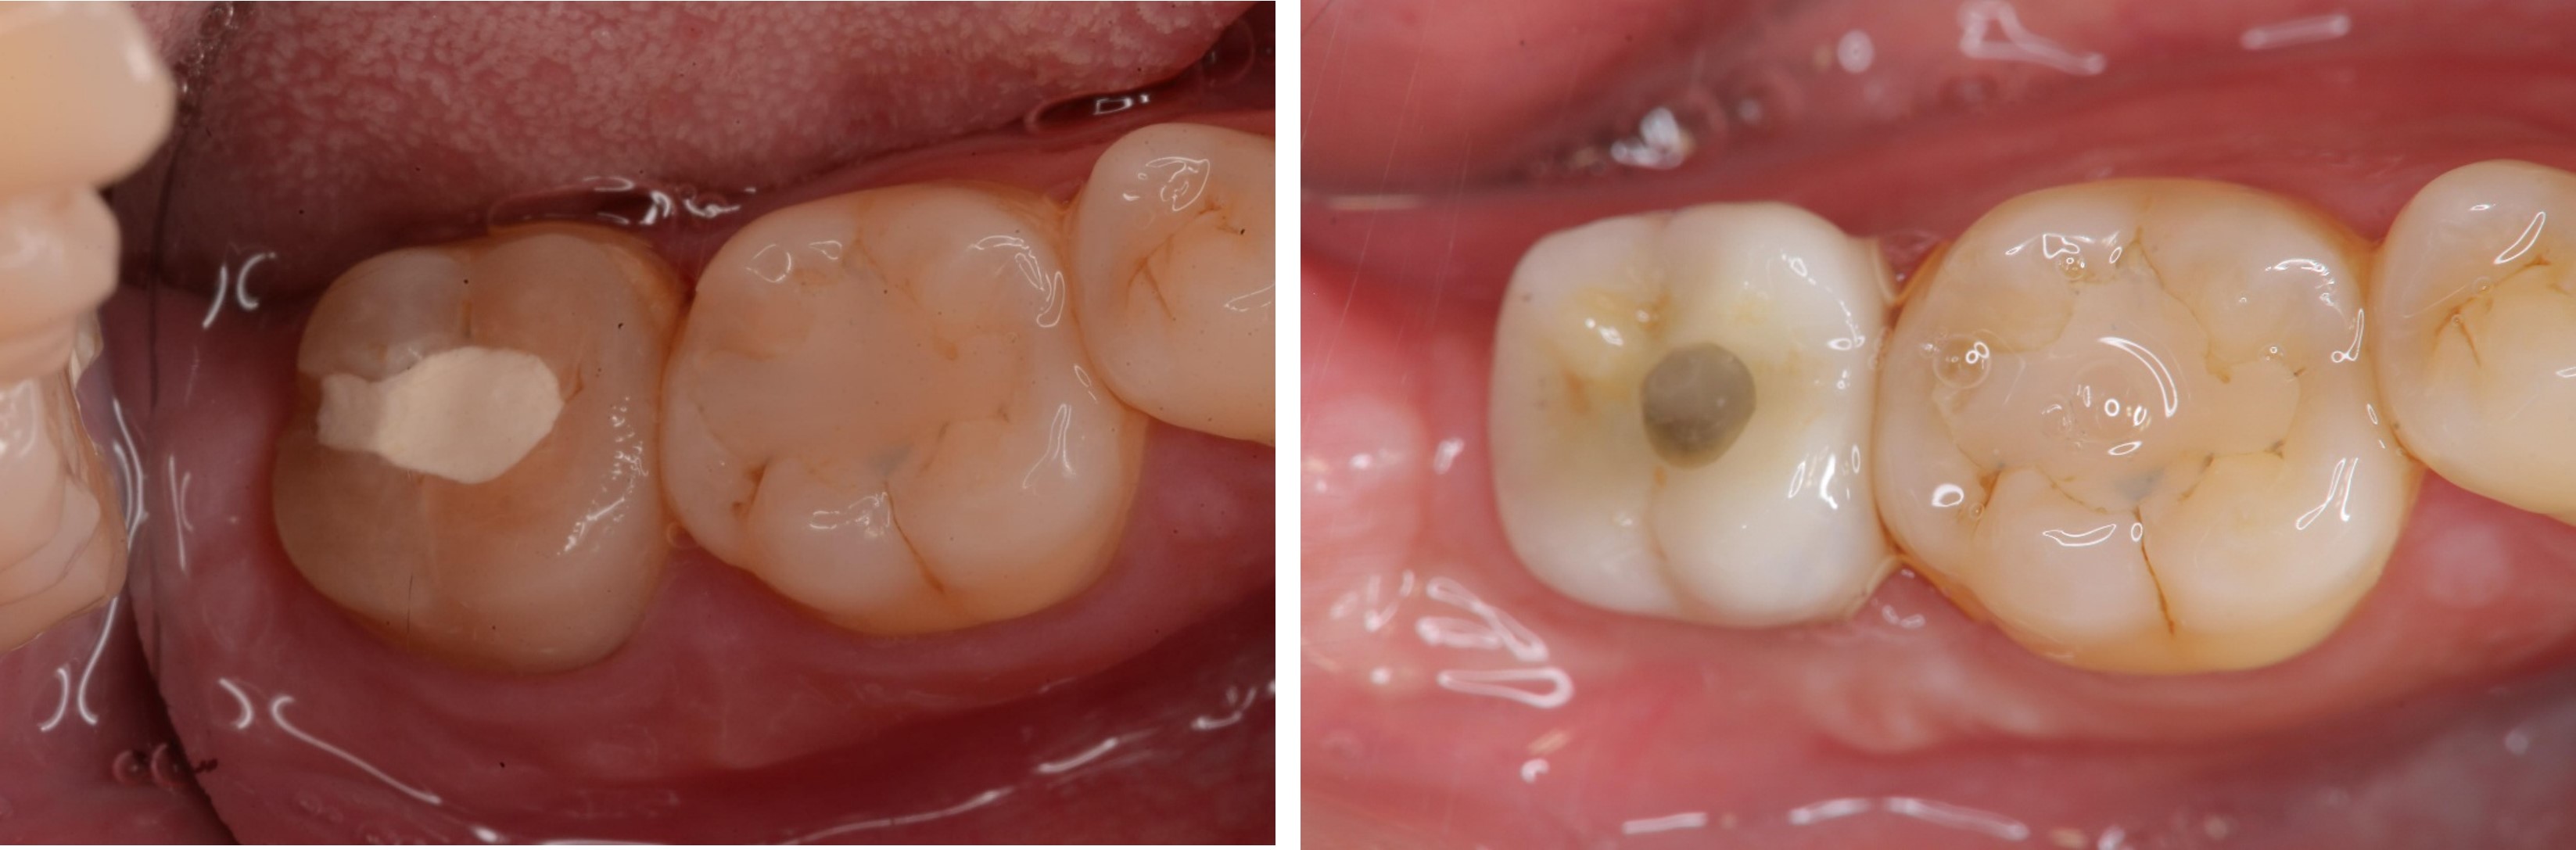

陶瓷冠蓋體-蛀牙-#46

審美牙科

瓷塊-冠蓋體